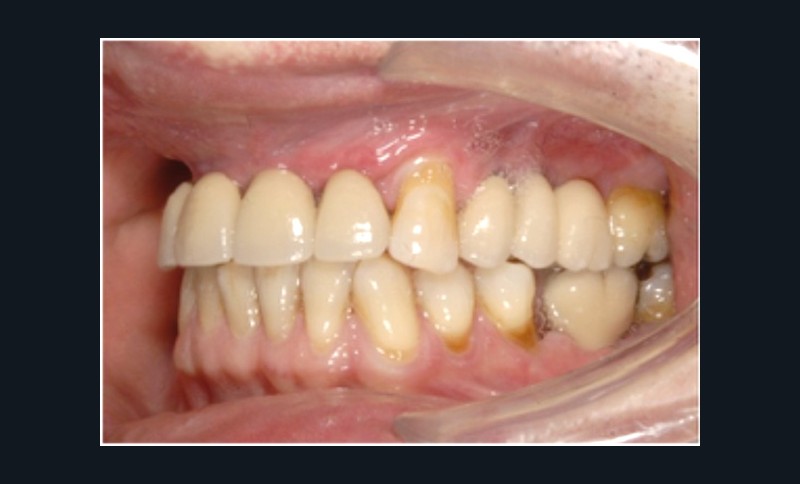

Cette partie de la présentation ne se contentait pas de rapporter les principes précédemment décrits à des régions limitées des maxillaires mais étendait la discussion à la difficulté majeure rencontrée en implantologie : rattraper des erreurs de positionnement implantaire ayant entraîné des compromis prothétiques inesthétiques. La solution thérapeutique mise en œuvre par Benoît Philippe consiste à appliquer la procédure d’ostéotomie segmentaire à l’entité constituée par l’os alvéolaire péri-implantaire et les implants. Les couronnes implantaires sont déposées. Le tracé d’ostéotomie encadre le segment à repositionner mais n’implique pas la corticale palatine qui sera fracturée pour éviter toute lésion du périoste (nourricier du segment alvéolo-implantaire). Un dispositif prothétique préparé en amont guide la translation du fragment qui est fixé au moyen de plaque d’ostéosynthèse dans la situation idéale. Le capital squelettique est reconstruit et l’espace prothétique disponible est normalisé.

Au cours de la conférence, Benoît Philippe a énoncé ses convictions concernant les conditions de succès du traitement implanto- prothétique : le respect d’une biomécanique implantaire équilibrée, le recours à des implants plus fins et moins nombreux que ne l’imposaient les préconisations d’autrefois, l’observation du biotype parodontal plus ou moins favorable aux reconstructions des atrophies étendues, la nécessité de restaurer au préalable puis de maintenir un environnement parodontal satisfaisant (en particulier la gencive attachée péri-implantaire).